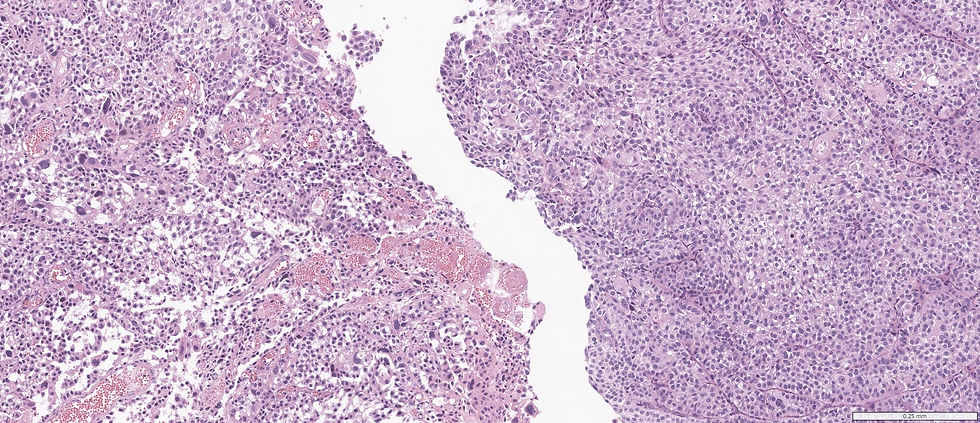

Case 3:

3. What's your diagnosis?

A. Carcinoma in situ

B. Dysplasia

C: Low grade papillary carcinoma, non-invasive

D: High grade papillary carcinoma, non-invasive

E: Invasive papillary carcinoma

Case 1: High grade papillary carcinoma, non-invasive; Case 2: High grade papillary carcinoma, non-invasive; Case 3: Invasive papillary carcinoma.